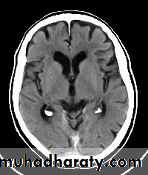

Normal Ventricles

Hydrocephalus